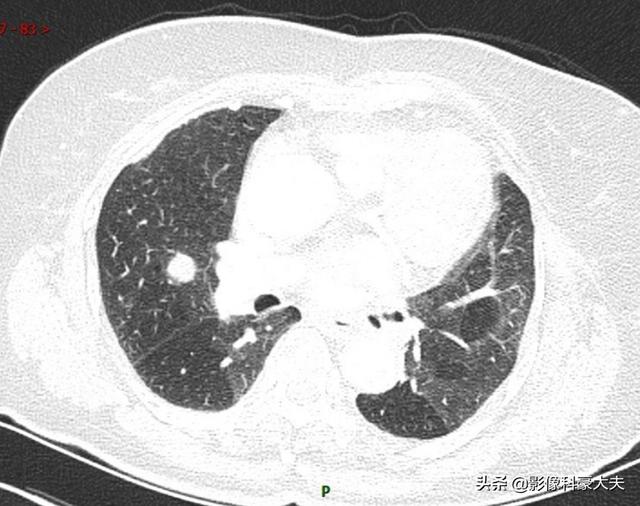

Cette patiente présentait un nodule pulmonaire de 1,1 cm, absent il y a trois mois, et l'examen anatomopathologique a révélé un adénocarcinome pulmonaire métastatique.